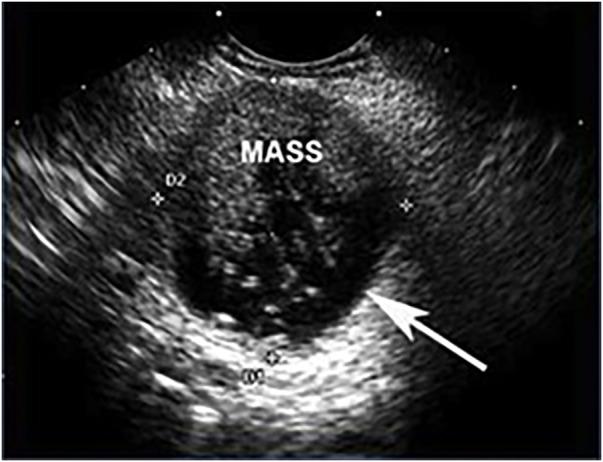

Pancreatic cystic lesions can be benign, premalignant or malignant. The recent increase in detection and tremendous clinical variability of pancreatic cysts has presented a significant therapeutic challenge to physicians. Mucinous cystic neoplasms are of particular interest given their known malignant potential. This review article provides a brief but comprehensive review of premalignant pancreatic cystic lesions with advanced endoscopic ultrasound (EUS) management approaches. A comprehensive literature search was performed using PubMed, Cochrane, OVID and EMBASE databases. Preneoplastic pancreatic cystic lesions include mucinous cystadenoma and intraductal papillary mucinous neoplasm. The 2012 International Sendai Guidelines guide physicians in their management of pancreatic cystic lesions. Some of the advanced EUS management techniques include ethanol ablation, chemotherapeutic (paclitaxel) ablation, radiofrequency ablation and cryotherapy. In future, EUS-guided injections of drug-eluting beads and neodymium:yttrium aluminum agent laser ablation is predicted to be an integral part of EUS-guided management techniques. In summary, International Sendai Consensus Guidelines should be used to make a decision regarding management of pancreatic cystic lesions. Advanced EUS techniques are proving extremely beneficial in management, especially in those patients who are at high surgical risk.